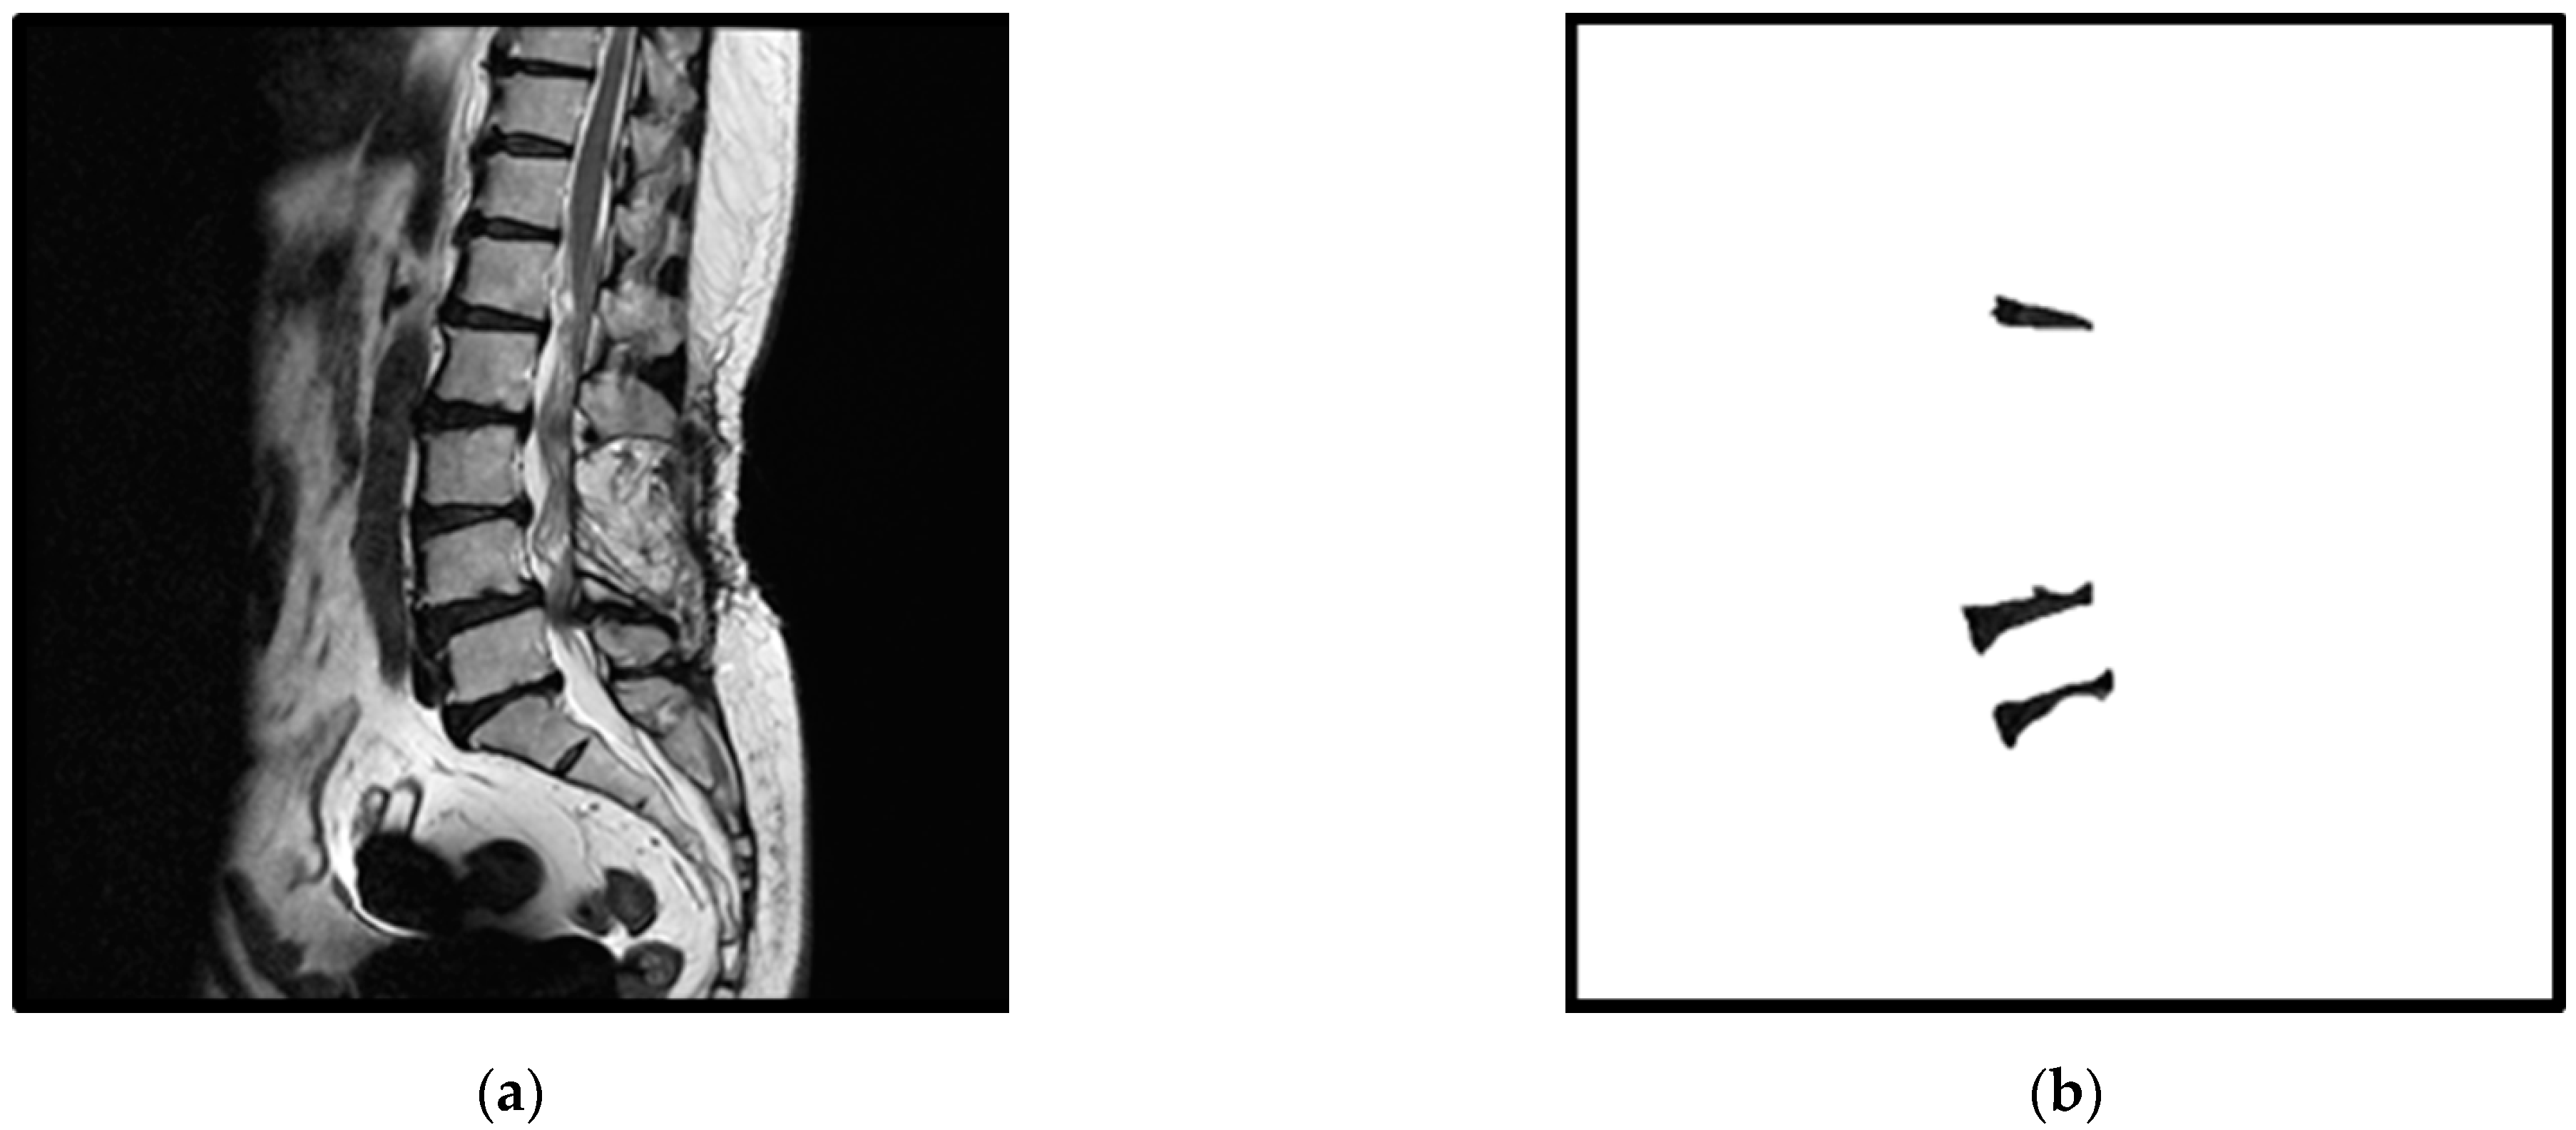

2. Materials

Figure 1.

An example of an original spine MRI image and its corresponding standard masks of the three considered intervertebral discs: (a) the original spine MRI image; (b) the corresponding standard masks of the three intervertebral discs of (a).